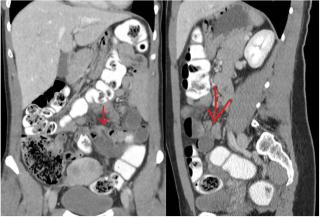

Case presentation

A 31-year-old previously healthy woman, with no surgical history, presented with sudden-onset, severe peri-umbilical abdominal pain unresponsive to high-dose opioids. CT-scan revealed mildly dilated distal jejunum with mesenteric edema and free fluid (Fig. 1, 2). Because of persistent pain despite step III analgesia, emergency diagnostic laparoscopy was performed. Intraoperatively, a closed-loop obstruction of an ileal segment was identified, herniated through a narrow internal window formed by an adherent mesenteric vessel supplying a Meckel’s diverticulum (Fig. 3). The vascular band was divided, releasing the closed loop, with no irreversible small bowel ischemic damage. The Meckel’s diverticulum was resected. The post-operative course was uneventful, and the patient was discharged after two days.